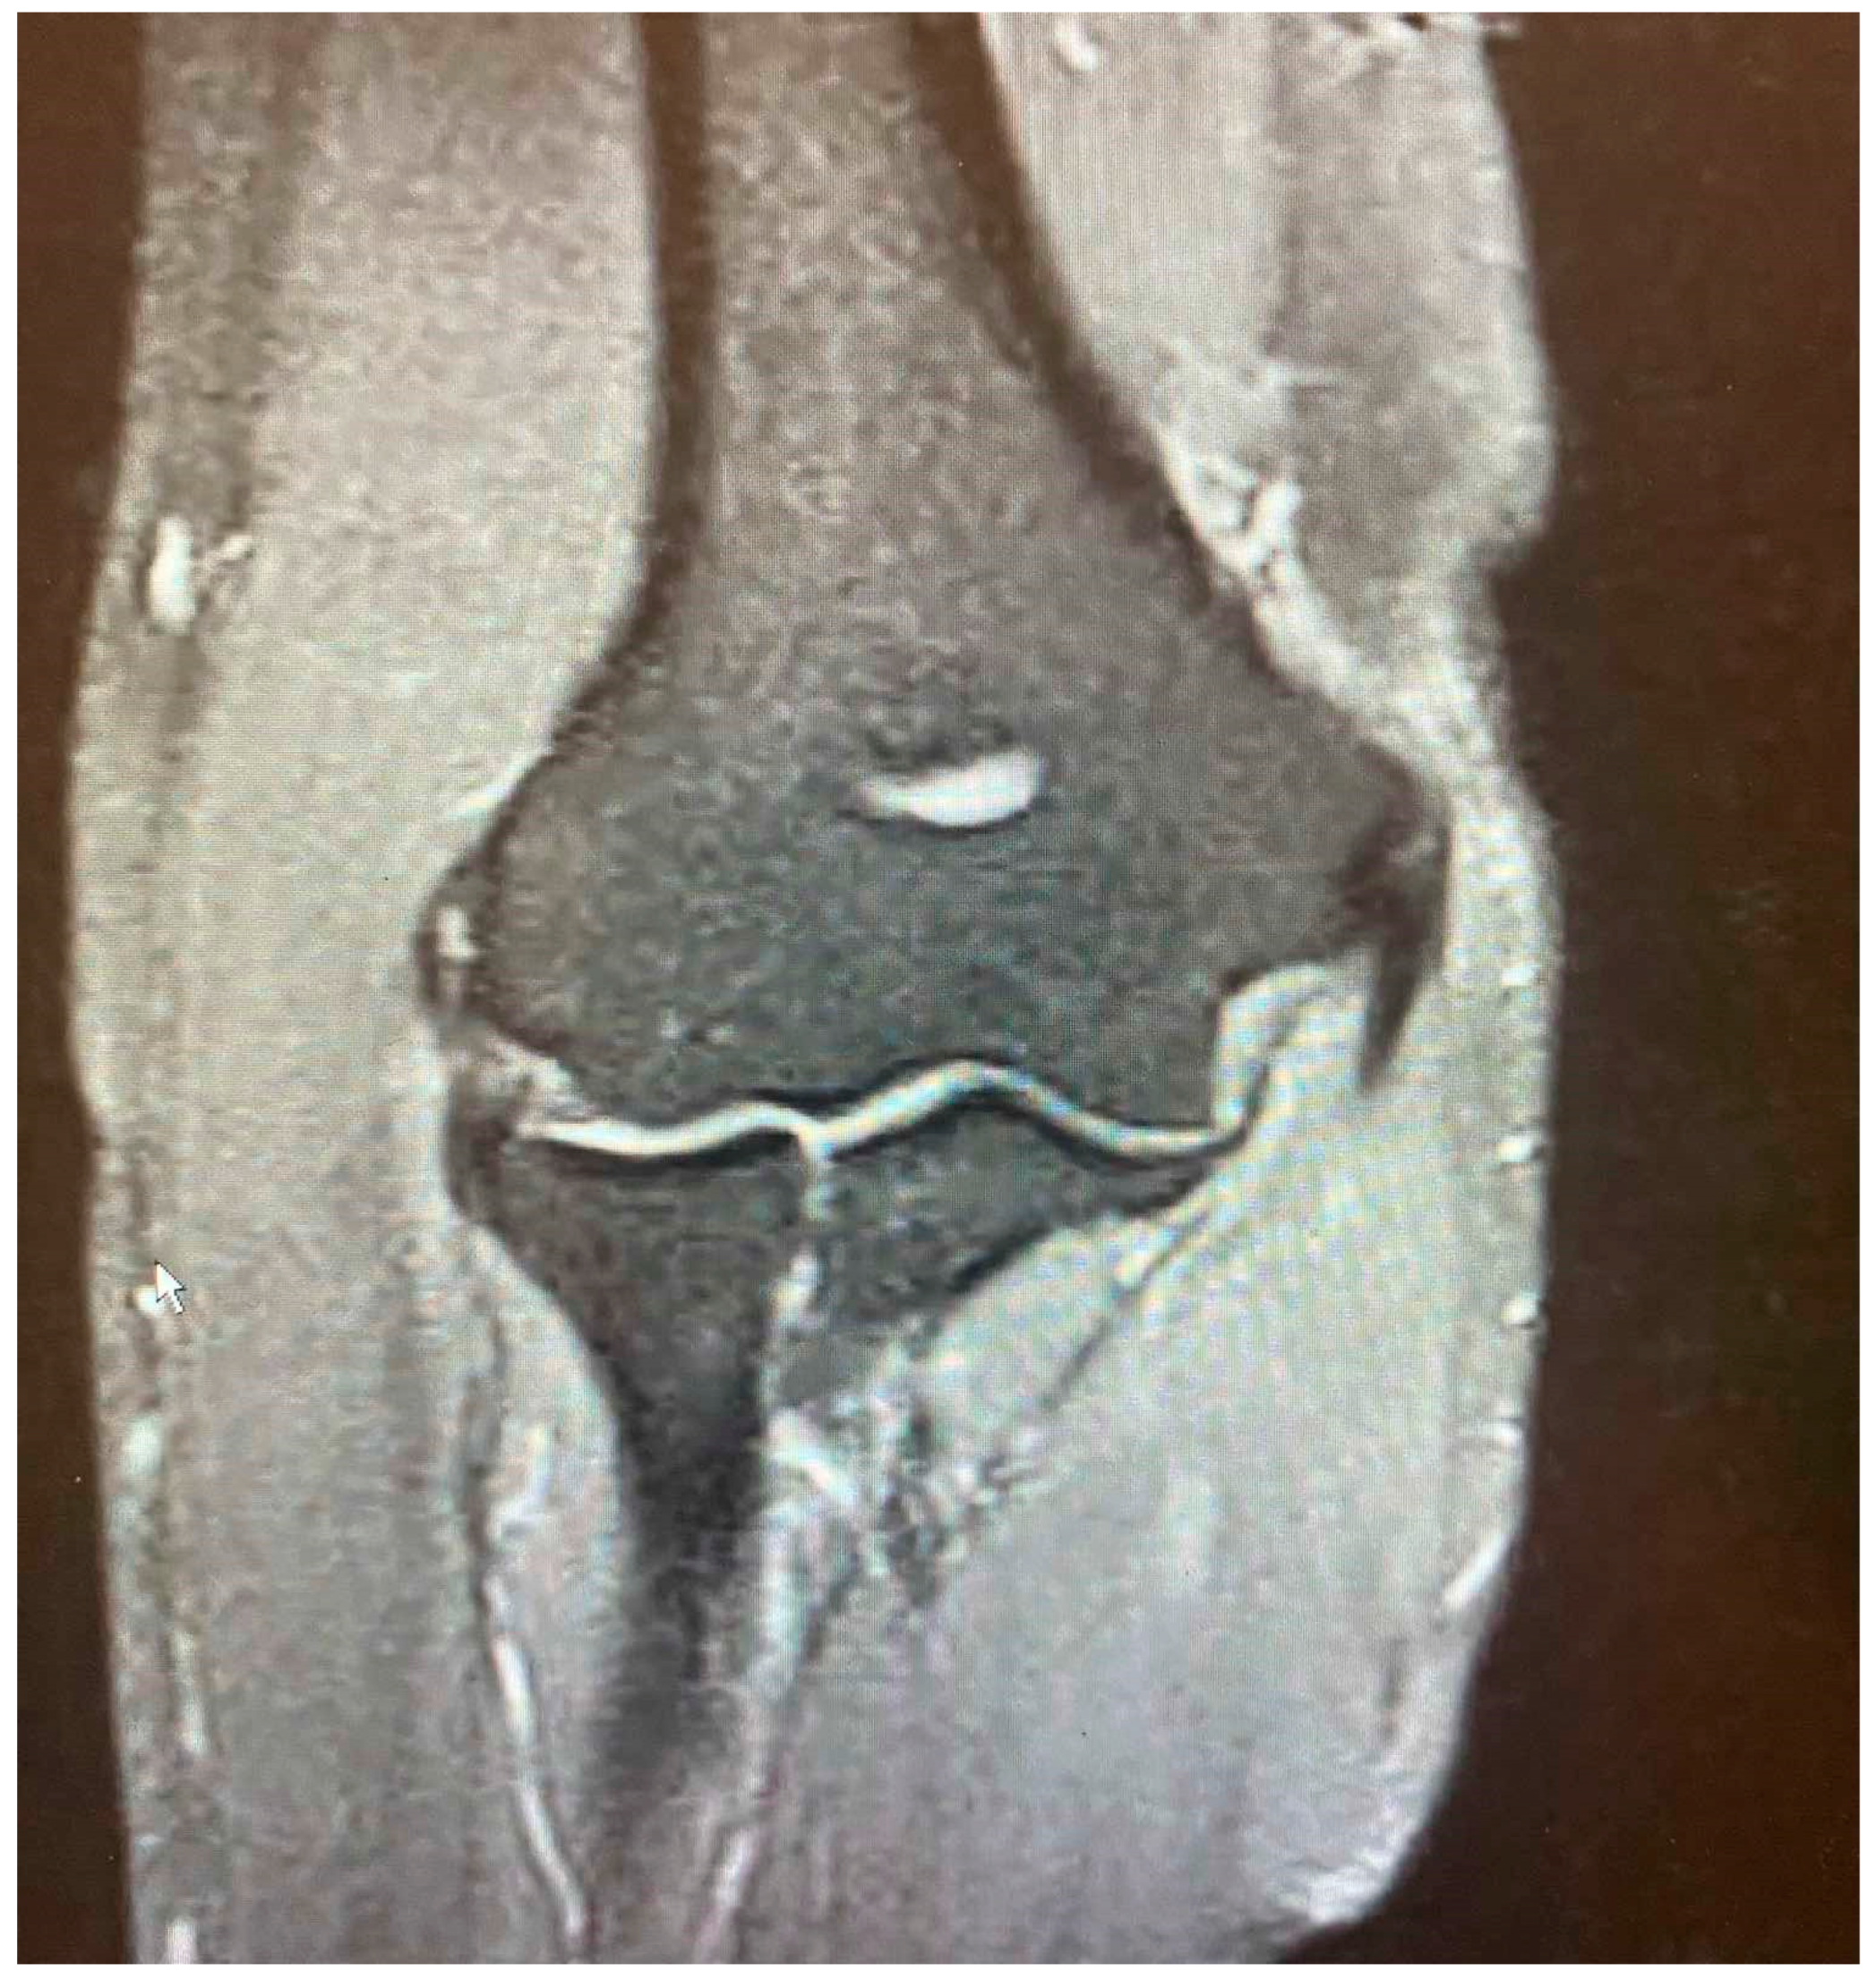

Figure 2.

Minor partial CEO tear [courtesy of C.K.].